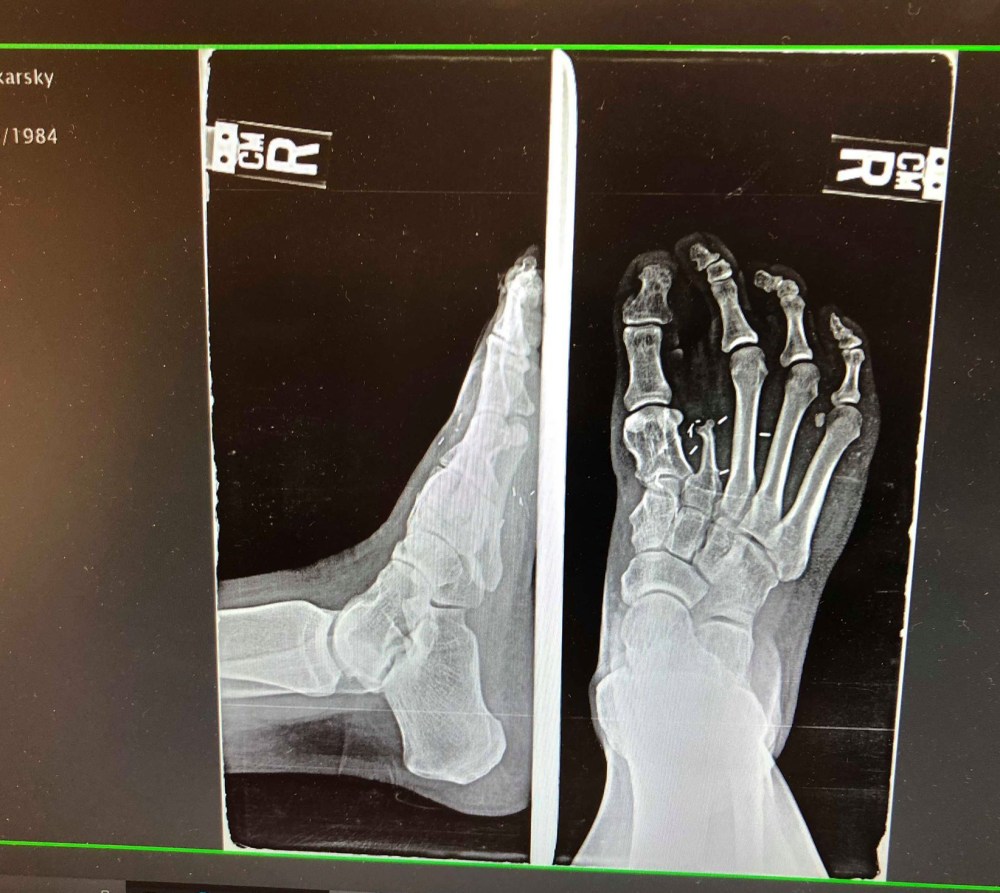

X-ray of my right foot… It’s 4 sizes smaller than my left foot, missing a toe, a big portion of bone from my big toe and still has staples in there from a lawn mower accident when I was 2 years old and multiple corrective surgeries. Was told by doctors I would probably never walk without a limp or be able to do normal physical activities like other kids. Grateful beyond words for my parents, family and coaches that never let me believe this was a disability. Gosh, how great of an excuse would this be to use and how different my life could look right now. But because I was taught to believe it was something special that made me stronger…that’s what I did with it instead. The mind is powerful friends. What you believe about things becomes your reality.